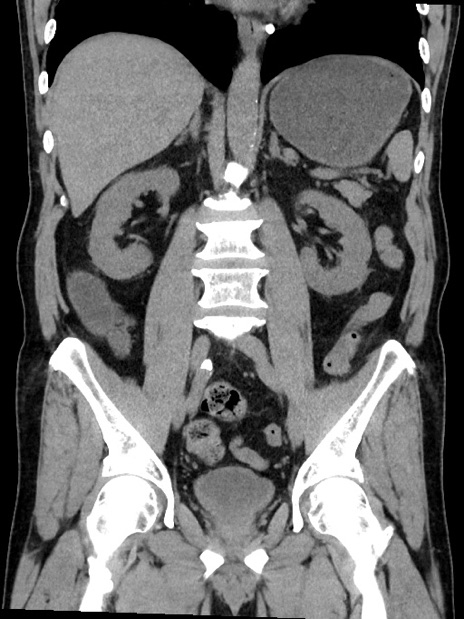

症例35(冠状断像)

【症例】70歳代 男性

【主訴】腹部膨満、嘔吐

【現病歴】昨日より腹部膨満感出現。本日増悪し、仙痛出現。嘔吐あり、受診。

【既往歴】糖尿病、胆摘後

【身体所見】BP 149/80mmHg、HR 74/min、BT 35.9℃、腹部:膨満、軟、圧痛なし。腸雑音減弱あり。上腹部正中切開瘢痕あり。

【データ】WBC 13500、CRP 1.72